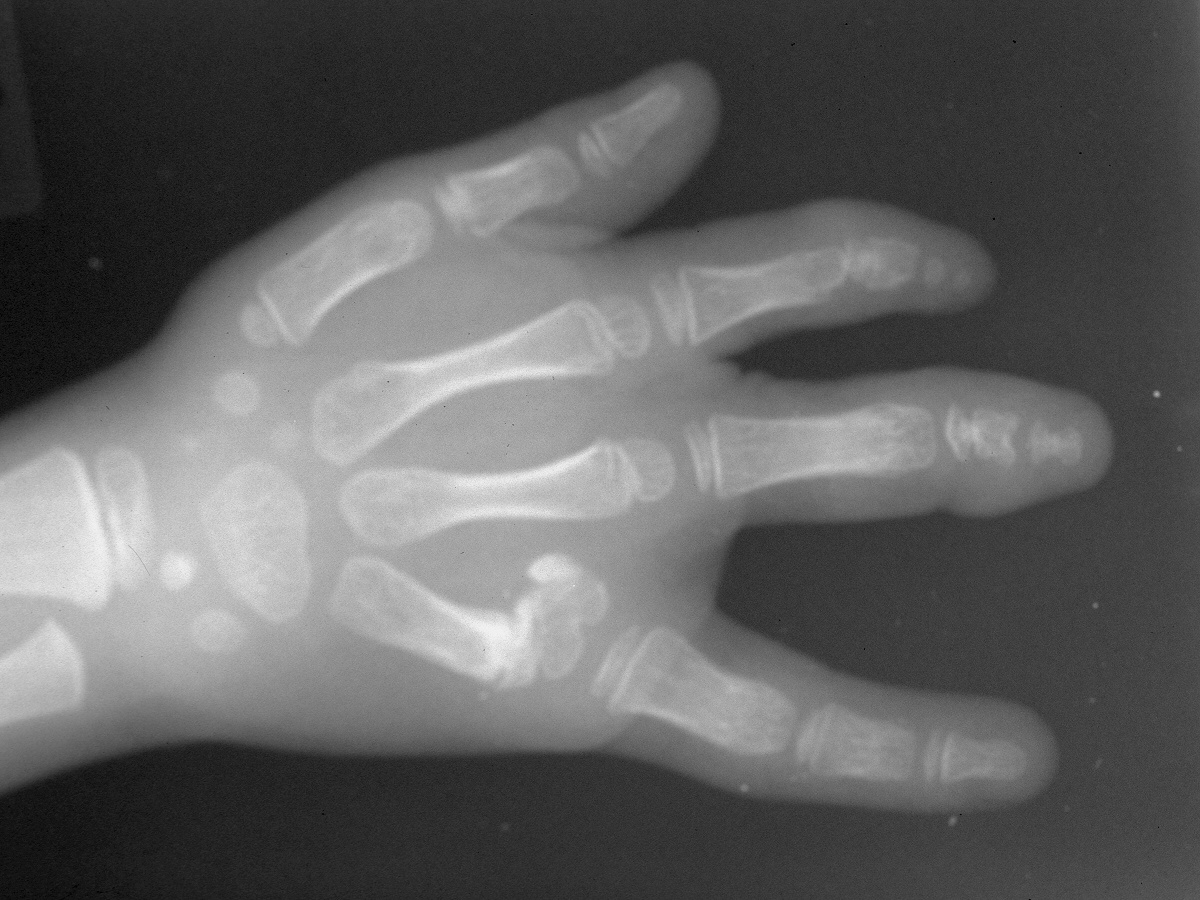

Further growth allowed better evaluation of the ulnar skeletal components.

The second procedure included web deepening with a three-flap plasty and closing wedge osteotomy to realign the small finger  metacarpophalangeal joint.

Postop Xray.